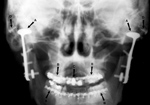

Temporomandibular prosthetic condyle implant (A); orthodontic arch bars (B); porcelain veneer dental crowns (caps) (C); fixation screws (bone screws) (D) |